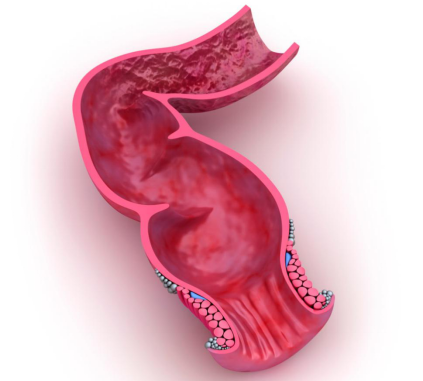

食管扁长、细软,最大直径仅有2厘米,还有三个生理狭窄处,这些特性令异物尤其容易停留。

狭窄是受气管、血管或隔膜压迫形成的,一旦穿破,就可能危及旁边的重要结构。图片来源《局部解剖学》据统计,消化道嵌顿事故有75%发生在食管,而且大都发生在前两个狭窄处。

异物停留在食管是非常危险的,因为食管不仅用处不大,还很脆弱。它的正常厚度只有大约0.5厘米,这一层薄薄的肉质管道,一旦有尖锐的异物,如鱼刺、骨头、枣核等进入,就非常容易被划破。雪上加霜的是,食管周围都是重要脏器:有气管、主动脉、肺部、心脏,假如锐器穿过食管在胸腔里来一场说走就走的旅行,后果将不堪设想。食管平常是扁扁的,有东西吞下时会被撑开。图片来源 Gifsoup有食管异物的病人常常能够感觉到嵌顿部位的明显不适,检查确诊后,只要食管没有明显的炎症反应就要尽快通过内镜取出,因为异物停留的时间越长,局部的肿胀、后续的风险就会越大。